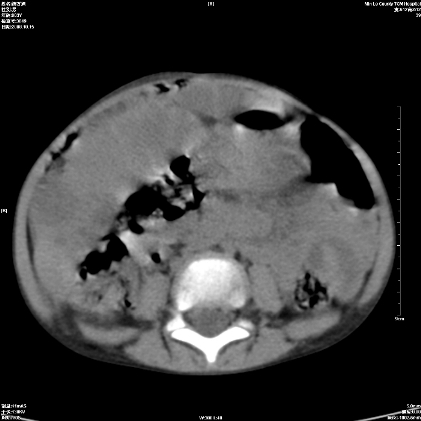

标题: PED1609:男性,3岁。彩超示肝Ca. [打印本页]

标题: PED1609:男性,3岁。彩超示肝Ca.

3岁;肝低密度灶;有钙化;有转移灶;考虑肝母细胞瘤;查afp

支持肝母细胞瘤肝内转移

考虑神经母细胞瘤并肝转移